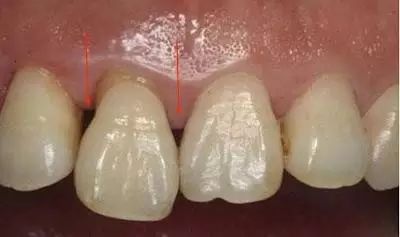

如果两颗牙齿之间的牙龈乳头退缩(牙龈萎缩),就会造成两颗牙齿之间下方出现空隙,食物就比较容易在嘴唇、脸颊和舌头的运动作用下,水平地进入了间隙,造成了塞牙的现象。